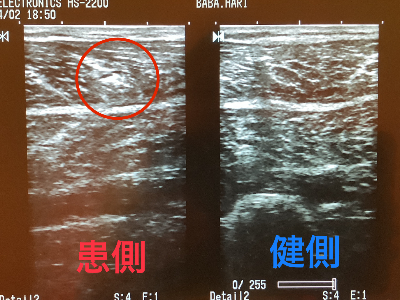

症例14

40代 男性 大阪府 競輪選手 2024年4月受診

練習で階段のダッシュを繰り返し、下腿部に違和感が出ていた。後のレースで下踏み込んだ際に肉離れを発症する。

右下腿部肉離れ

超音波エコー検査

肉離れのエコー画像

筋肉の早期修復を目指し、受傷部位にマイクロカレント通電。